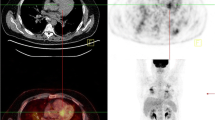

The maximum standardized uptake value (SUVmax) has been used for semiquantitative measurements to assess the intensity of 18F-FDG uptake. Recently, the availability of volume-based analysis, such as metabolic volume and total lesion glycolysis, has been widely used to evaluate the extent and activity of the 18F-FDG uptake in malignant tumors [15]. Ahmadian et al. applied volume-based analysis to cardiac sarcoidosis and reported that the metabolic activity estimated by 18F-FDG PET was a reliable independent predictor of cardiac events in cardiac sarcoidosis patients [16]. A volume-based quantification of 18F-FDG uptake could be of value in a number of fields of cardiac and inflammation diseases like it is for malignant tumors (Fig. 16.4).

Representative case.

This is a case of a cardiac sarcoidosis patient with uveitis and respiratory discomfort. She had a right bundle branch block and right axis deviation on the electrocardiograph and thinning of the septal wall with severe hypokinesis on the echocardiograph. There was a clearly abnormal 18F-FDG uptake in the LV wall as well as in the lymph nodes which indicated active inflammatory changes associated with sarcoidosis (a). The estimated maximum standardized uptake value (SUVmax) was 10.6, and the volume of the uptake was 76.1 ml (the threshold was obtained from the liver uptake) at the cardiac lesion. The 18F-FDG PET [revealed the dramatic] showed a nearly total disappearance of the abnormal cardiac uptake after 4 weeks of therapy with prednisolone (b). However, the 18F-FDG PET during the tapering of the prednisolone showed renewed 18F-FDG uptake. Here, the estimated maximum standardized uptake value (SUVmax) was 6.2, and the volume of the uptake was 7.83 ml (the threshold was obtained from the liver uptake). This case indicates that 18F-FDG was useful to evaluate the sarcoidosis activity and indicated the improvement during the therapy as well as the recurrence of the active sarcoidosis